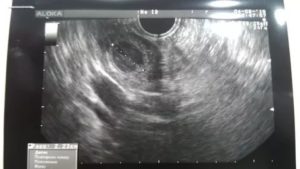

Процедура трансвагинального УЗИ

УЗИ плода трансвагинальным методом можно делать женщинам на ранних сроках беременности, но не позднее 12 недель.

Во время обследования специальный датчик вводится во влагалище. Пациентка должна расслабить мышцы тазового дна и следить за своим дыханием.

Когда врач проводит прибором по нижней стенке влагалища, допускается наличие дискомфорта, но не острой боли.

Но если после 12 недели проводится ультразвуковое наружное исследование, то до этого срока делается вагинальное УЗИ.

Во время него используется специальное устройство в виде трубки оснащенной камерой, которая подается во влагалище женщины и выводит изображение на монитор компьютера.

Такое УЗИ считается наиболее информативным, так как оно позволяет получить полную картину о состоянии репродуктивных органов и о протекании беременности.